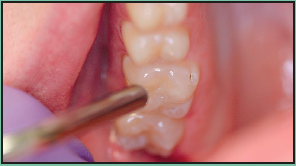

Figure 2 - Teeth to be sealed isolated with a dental dam

Figure 2